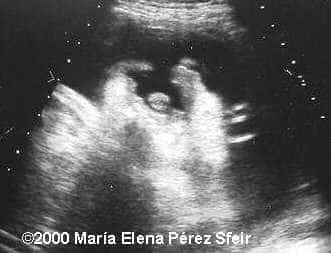

Cleft-lip, unilateral MarÃa Elena Pérez Sfeir, MD Article Published: May 30, 2002 Patagonia, Argentina This is an example of cleft-lip in a 3rd trimester fetus. Discussion Board Start a discussion about this article Add to Favorites Favorite